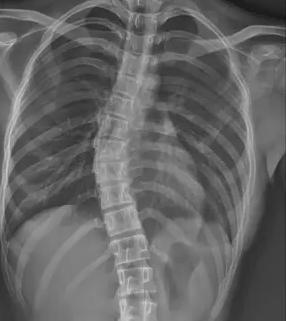

當(dāng)前青少年脊柱側(cè)彎診療體系面臨系統(tǒng)性困境。在篩查環(huán)節(jié),傳統(tǒng) X 線測(cè)量 Cobb 角雖為金標(biāo)準(zhǔn),但輻射風(fēng)險(xiǎn)限制其大規(guī)模應(yīng)用;現(xiàn)有初篩手段假陽(yáng)性率高達(dá) 35%,而低輻射智能篩查技術(shù)在基層醫(yī)院普及率不足 12%,導(dǎo)致大量病例漏診。疾病管理鏈條存在顯著斷層,Cobb 角<10° 的輕癥患者因缺乏標(biāo)準(zhǔn)化干預(yù)方案,錯(cuò)失黃金矯正期。保守治療領(lǐng)域,支具治療依從性不足 40%,定制精度誤差超 15%,全國(guó)注冊(cè)矯形師缺口達(dá) 83%;物理治療資源配置失衡,70% 的基層醫(yī)療機(jī)構(gòu)尚未建立規(guī)范康復(fù)訓(xùn)練體系。

針對(duì)上述痛點(diǎn),醫(yī)療科技企業(yè)與科研機(jī)構(gòu)正聯(lián)合構(gòu)建智慧防治體系。迪納醫(yī)療研發(fā)的全幅 Dira-DUC 技術(shù),通過(guò) AI 輔助三維重建實(shí)現(xiàn)單次 0.02mSv 低劑量成像,較傳統(tǒng)設(shè)備輻射量降低 87%。其自主研發(fā)的脊柱側(cè)彎風(fēng)險(xiǎn)預(yù)測(cè)模型,整合 120 萬(wàn)例臨床數(shù)據(jù),可精準(zhǔn)識(shí)別高危人群,篩查準(zhǔn)確率提升至 92%。診療環(huán)節(jié)引入智能 Cobb 角測(cè)量算法,將人工測(cè)量誤差從 ±5° 壓縮至 ±1.2°。在支具治療方面,智能監(jiān)測(cè)支具內(nèi)置壓力傳感器與物聯(lián)網(wǎng)模塊,實(shí)時(shí)反饋佩戴數(shù)據(jù)并生成個(gè)性化調(diào)整方案。物理治療領(lǐng)域,標(biāo)準(zhǔn)化訓(xùn)練課程已納入國(guó)家衛(wèi)健委基層康復(fù)指南,配備 AI 動(dòng)作捕捉系統(tǒng)的智能訓(xùn)練艙正在全國(guó) 127 家縣級(jí)醫(yī)院推廣。